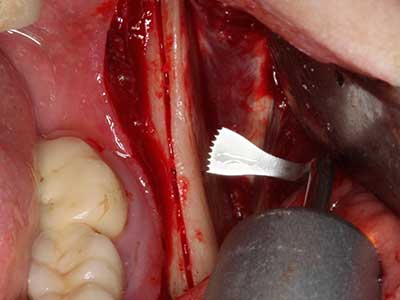

Bei der Knochenblockentnahme zeigen sich weitere Vorteile für die Piezochirurgie: Neben der bereits beschriebenen hohen Präzision bei der Osteotomie stellt sich gerade die Verwendung der dünnen Sägespitzen als besonders materialschonend heraus. Bei der Verwendung insbesondere von Lindemannfräsen sind mit deutlich höheren Entnahmeverlusten durch die dickere Instrumentenspitze zu rechnen (Lakshmiganthan, Gokulanathan et al. 2012). Die insbesondere bei retromolar entnommenen Blocktransplantaten notwendige basale Abtrennung wird durch speziell hierfür vorgesehene rechtwinklige Sägen erleichtert, so dass die Piezochirurgie als präzises, übersichtliches und sicheres Verfahren zur retromolaren Knochenblockgewinnung angesehen wird (Happe 2007) (Abb. 1-12).